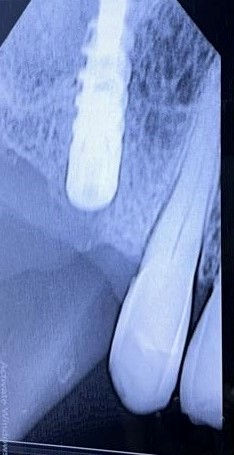

The various prosthetic treatment options for malpositioned implants are outlined in Table 1. Malpositioned implants may result from multiple surgical and prosthetic errors; Figures 1–3 highlight the various positional errors encountered in dental implant placement.

Figure 1. Retained root adjoining the dental implant.